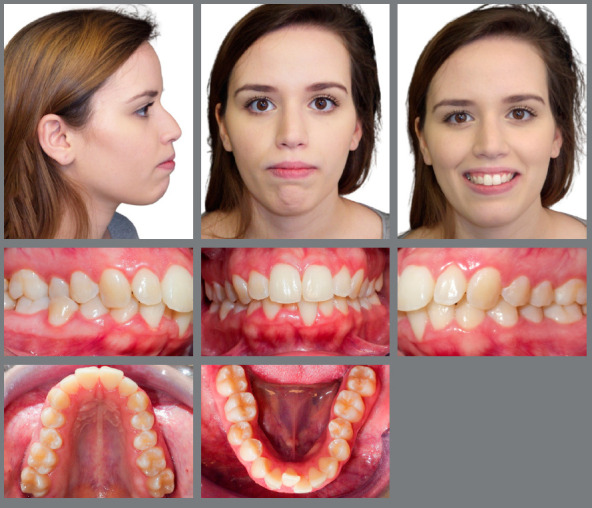

Objective: To describe the treatment of a 23-year-old woman with an Angle Class II, division 1 malocclusion with constricted maxillary and mandibular arches.

Case report: The patient's main complaint was mandibular anterior crowding. The treatment plan included expansion of the mandibular arch concurrent with maxillary expansion, using a MARPE appliance in combination with a full-fixed appliance to align and level the crowded mandibular teeth, along with miniscrews as anchorage for the maxillary teeth and for distalization of the molars and premolars. A successful non-extraction orthodontic treatment was accomplished after 28 months, and the occlusion and teeth alignment, as well as facial goals, were resolved in a clinically satisfactory manner.

Conclusion: The treatment objectives were met, and the outcome of the expansion of the maxillary arch with a MARPE appliance as an adjunct to a fixed appliance was considered a success. An esthetic, functional, and stable result after a 1-year follow-up was achieved and was satisfactory to the patient.